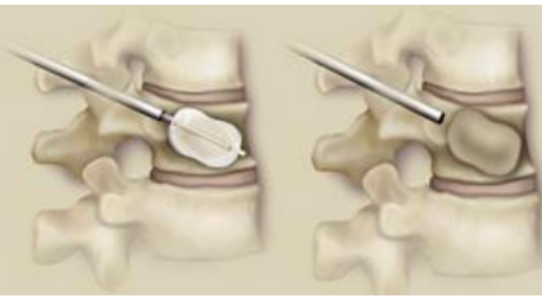

椎体强化手术,包括椎体成形术(PVP)和经皮球囊扩张椎体后凸成形术(PKP),是目前最常用的微创手术治疗方法。通过经皮向骨折椎体注射骨水泥,能够迅速缓解疼痛,增强病椎的强度和刚度,防止椎体进一步塌陷和畸形,而且没有传统开放手术内固定带来的手术创伤以及远期可能出现的内固定失败。PKP还可通过球囊扩张使压缩骨折得到一定程度的复位,球囊取出后在椎体内形成的空腔有利于骨水泥低压力注入,有效降低骨水泥渗漏率。

经皮球囊扩张椎体后凸成形术(PKP)

①正位、侧位影像监测下,经皮由椎弓根置入;

②置入导管球囊扩张,向气囊内充气扩张,以恢复椎体高度;

③放出气囊内气体,移走气囊,注入骨水泥维持矫正后形态